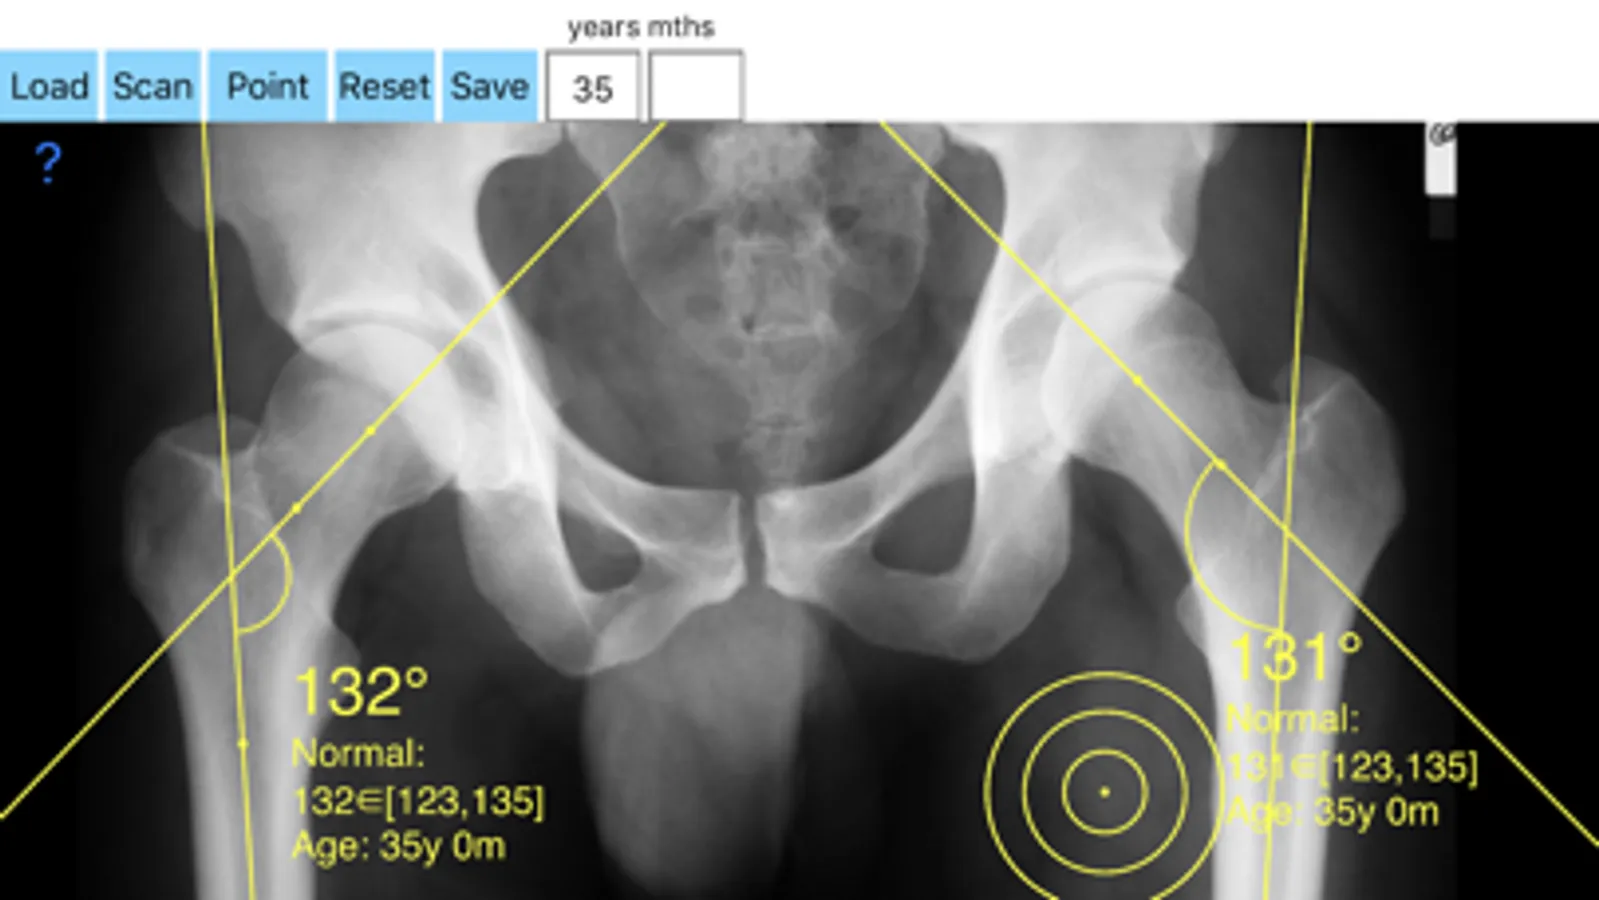

-Offers a very convenient way to determine the most accurate possibly lines in order to measure the angle. By the aid of a circular template, four points of interest are marked. The automatically formed lines drawn between points give an angle which is measured automatically by the App. The visualized results are in degrees.

By inputing the age of the patient in the App, the measured angle is compared with values from normal reference database (see reference) according the patient age. In case the measured angle is increased or decreased, the hip is valgus or varus respectively.